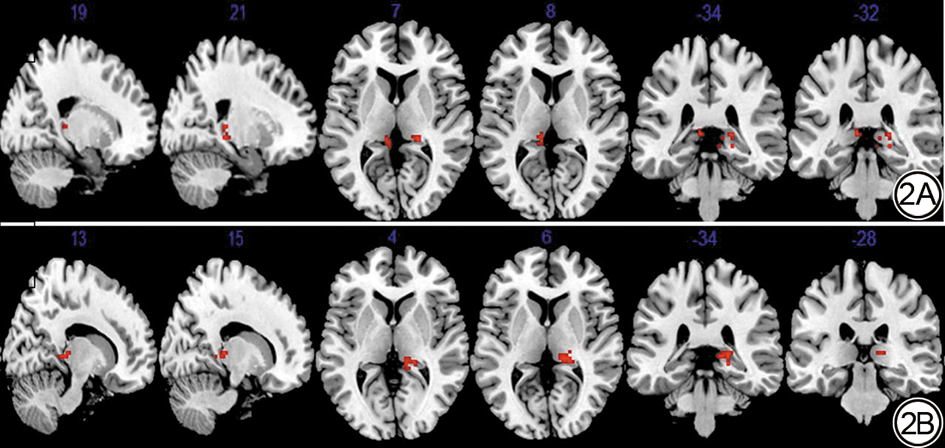

基于rs-fMRI数据,在全脑体素水平计算ReHo值,随后进行组间两两比较。差异脑区所在位置见图2,具体空间坐标、簇大小、t值及P值见表3

结果显示,与CSVD 2分组相比,CSVD 4分组在皮层的左侧颞极ReHo值显著升高,差异具有统计学意义(P=0.022)。在皮层下区域,CSVD 4分组的ReHo值在两侧丘脑均显著高于CSVD 2分组,差异具有统计学意义(P=0.017)。尤为显著的是,CSVD 4分组在右侧丘脑的ReHo值也显著高于CSVD 3分组,差异具有统计学意义(P=0.003)。

图2  基于全脑体素水平的脑小血管病(CSVD)不同总负荷组间的局部一致性(ReHo)差异结果。红色区域代表ReHo值升高的脑区,数字为对应脑区的蒙特利尔神经学研究所(MNI)坐标。2A显示总负荷4分组较2分组ReHo值升高的区域;2B显示总负荷4分组较3分组ReHo值升高的区域。

Fig. 2  Whole-brain voxel-level regional homogeneity (ReHo) differences among different total burden groups of cerebral small vessel disease (CSVD). Red regions indicate brain areas with increased ReHo values. Numbers indicate Montreal Neurological Institute (MNI) coordinates. 2A: Regions showing increased ReHo in the total burden 4 group compared to the total burden 2 group; 2B: Regions showing increased ReHo in the total burden 4 group compared to the total burden 3 group.